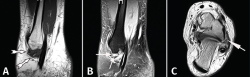

Figura 4. Resonancia magnética (RM) de un tobillo izquierdo en la que se aprecia un pinzamiento de partes blandas anterolateral. A: proyección sagital T1 que muestra un área de baja intensidad de señal que está desplazando la grasa normal (flechas blancas); B: proyección sagital STIR que confirma la presencia de tejido blando patológico (flecha); C: imágenes T2 axiales con tejido blando patológico anterolateral; la flecha apunta hacia un área de baja señal que corresponde a tejido patológico formado en el fascículo inferior del ligamento peroneoastragalino anterior (LPAA), que se ha lesionado crónicamente. Reimpreso con permiso de Foot and Ankle International: Ferkel RD, Tyorkin M, Applegate GR, Heinen GT. MRI Evaluation of Anterolateral Soft Tissue Impingement of the Ankle. Foot Ankle Int. 2010;31:655-61.

En 2010, Ferkel et al. señalaron la utilidad del diagnóstico mediante RM en este tipo de procesos(5). Los autores compararon los hallazgos quirúrgicos y los informes de RM de 24 pacientes con diagnóstico de presunción de pinzamiento anterolateral. En su estudio, utilizaron imágenes sagitales T1 y de recuperación axial de inversión (STIR) para confirmar el diagnóstico (Figura 4). Hallaron una precisión del 79%, una sensibilidad del 83% y una especificidad del 79% para el diagnóstico con RM de este tipo de procesos. Por ello, consideraron su empleo como determinante para el diagnóstico.